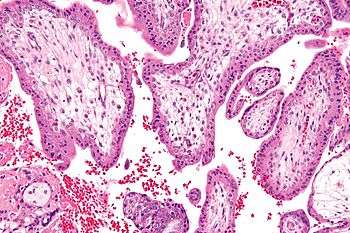

![]() Micrograph showing chorionic villi - the tissue that is collected in CVS. H&E stain. | |

Chorionic villus sampling (CVS), sometimes called "chorionic villous sampling" (as "villous" is the adjectival form of the word "villus"),[1] is a form of prenatal diagnosis to determine chromosomal or genetic disorders in the fetus. It entails sampling of the chorionic villus (placental tissue) and testing it for chromosomal abnormalities, usually with FISH or PCR. CVS usually takes place at 10–12 weeks' gestation, earlier than amniocentesis or percutaneous umbilical cord blood sampling. It is the preferred technique before 15 weeks.[2]